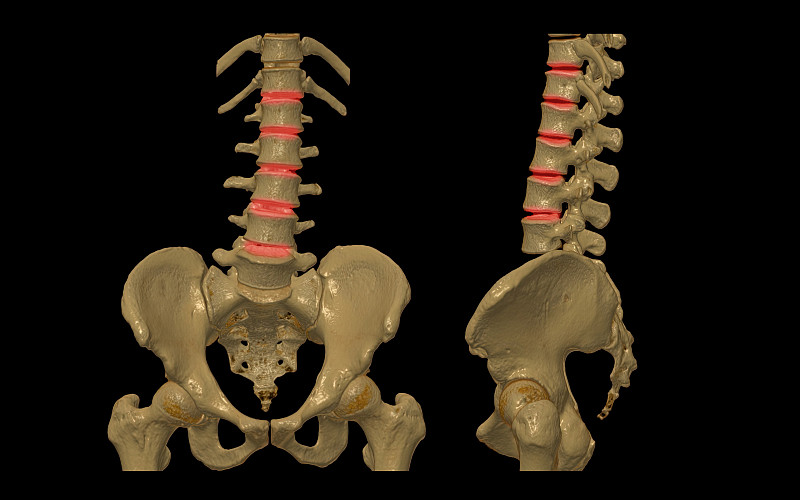

脊椎的3d插图渲染详情

人体骨盆详情